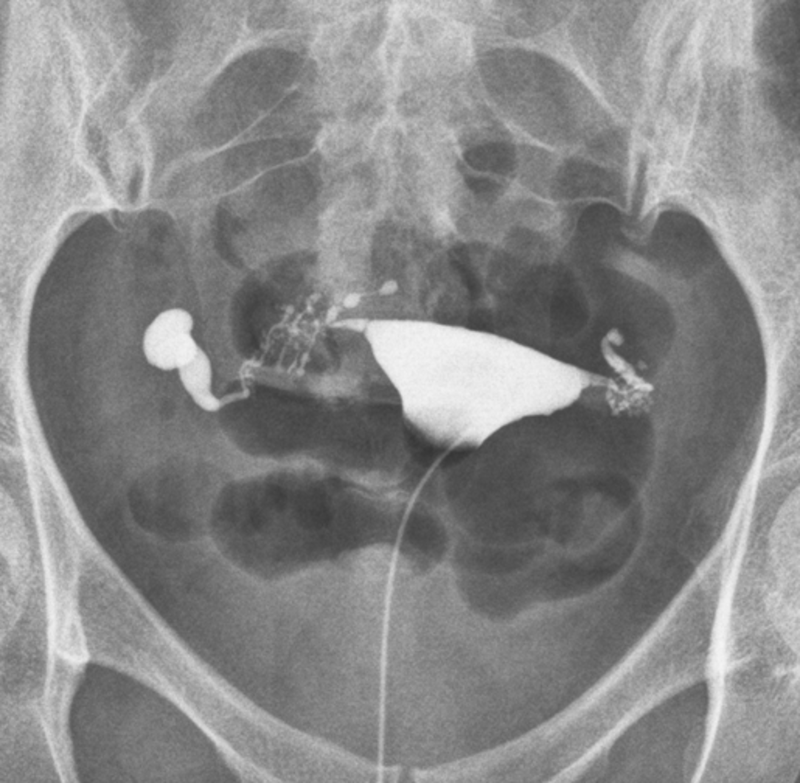

4.png

图4 出院记录,右侧输卵管近段结扎